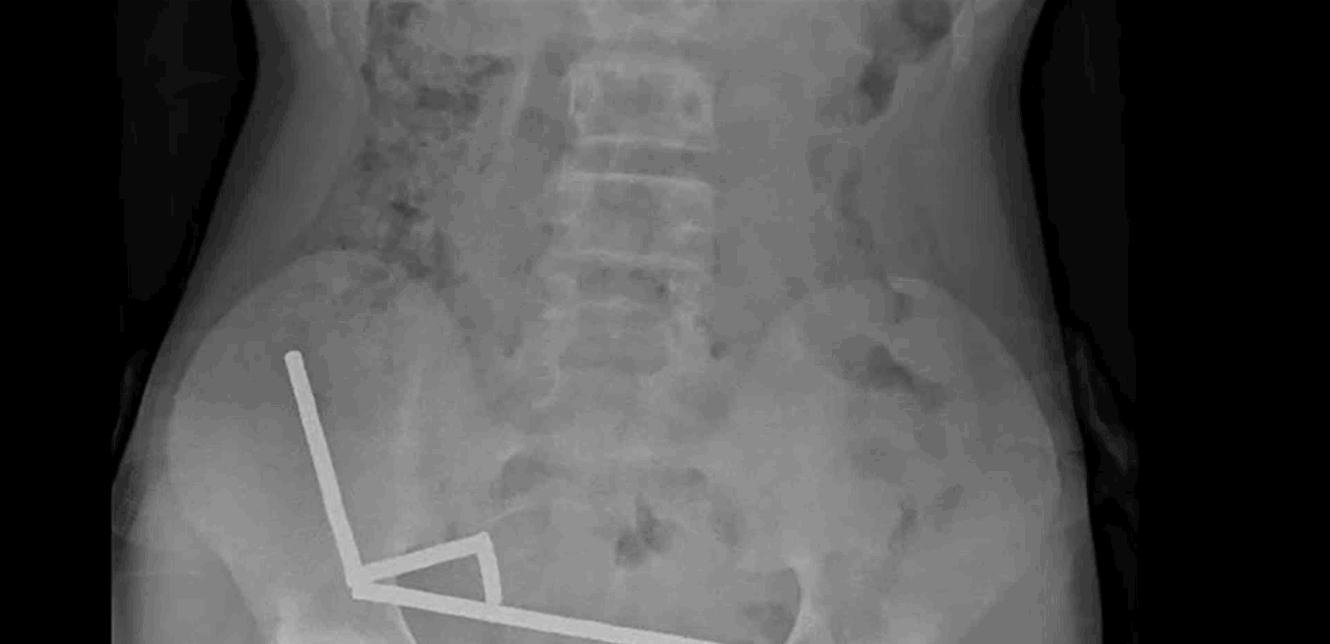

أظهرت صور الأشعة تجمع المغناطيسات في أربعة خطوط داخل الأمعاء "ملتصقة ببعضها بسبب القوى المغناطيسية"، ما سبّب تلفًا في الأنسجة.